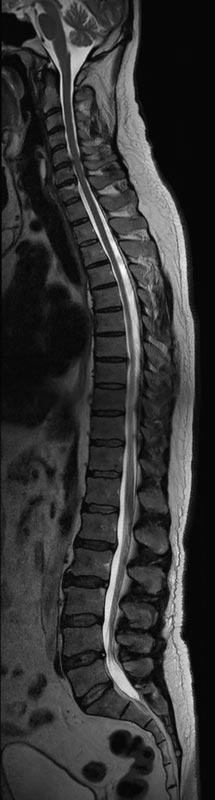

- Abklärung Bandscheibenvorfall

- Beurteilung Einengung des Rückenmarkkanals oder der Neuroforamina im Rahmen der degenerativen Wirbelsäulenerkrankung

- Tumor-/Entzündungsdiagnostik

- Multiple Sklerose

- Abklärung Spondylolisthesis

- Frakturdiagnostik (Alter und Ausdehnung der Fraktur) z.B. im Rahmen der Osteoporose